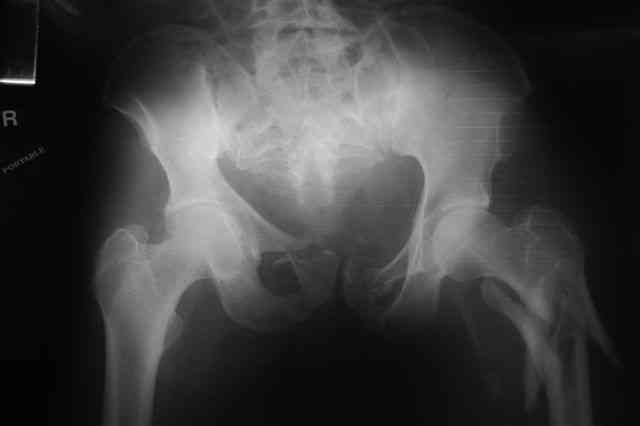

В приложении отправляю послеопер. снимки бедра и лодыжки обсуждаемого вчера больного.

Вчера прооперировал больного.

Попытка низвести половину таза на тракционном столе ( скелетное вытяжение за бедро) безуспешная.

из переднего доступа добрался до правого КП сочленения , все запаяно костью, с помощью 2 шанцев винтов в крестец и подвздошную кость и элеватора репозиция, контроль ЭОП

и двумя пластинами фиксация.

Спереди, аппарат как рекомендовал Джолдас.

Снимки плохого качества( очень темные) завтра переделают и пришлю на конференцию.

На мой взгляд, смещение устранено и фиксация выглядит вполне анатомичной.

В приложении послеоперационные картинки.